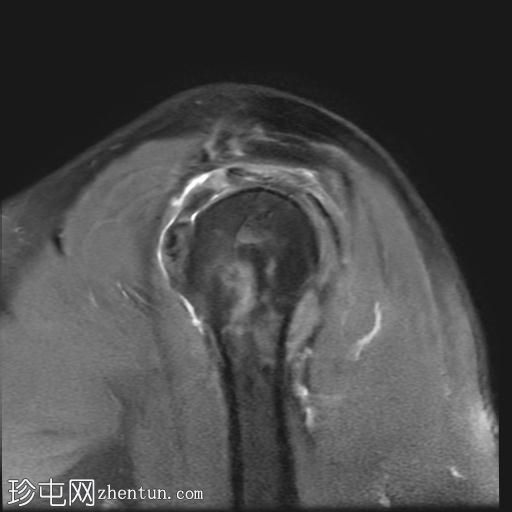

矢状位PD序列

脂肪抑制序列

冈上肌腱关节面中前部纤维可见部分撕裂(边缘撕裂),伴局部骨髓水肿。

冈上肌腱关键区纤维以及冈下肌腱均可见肌腱病。

肩锁关节周围可见轻度关节囊肥厚和退行性改变。

此外,肩峰下滑囊内可见积液。

MRI 检查结果符合冈上肌腱的典型边缘撕裂,也称为部分关节面肌腱撕脱。